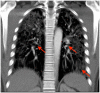

The second-generation anticonvulsant lamotrigine is widely used in the psychiatric field as a mood stabilizer or antidepressant augmentation therapy. Although particularly older anticonvulsants are known for their potential to cause hypersensitivity syndromes, newer antiepileptic drugs do hold a certain risk as well. Presenting a case of a 32-year-old male inpatient of African ethnicity suffering from a primary severe depressive episode in the course of a recurrent major depressive disorder, we report the occurrence of a rapid-onset drug-induced pneumonitis. Herewith, the interstitial pneumonitis occurred after the initiation of 25 mg lamotrigine as an augmentation therapy. Except for the clear temporal correlation between the administration of lamotrigine and the onset of pneumonitis, we did not reveal any further potentially causal diagnostic hints. Importantly, no relevant genetic variations of metabolizing enzymes or drug interactions resulting in lamotrigine overdosage as a potential cause of toxicity were identified. Our experience with a potentially life-threatening adverse drug reaction shortly after the initiation of the largely well-tolerated lamotrigine suggests a potential side effect under the second-generation anticonvulsant although similar adverse events are deemed to be very rare.